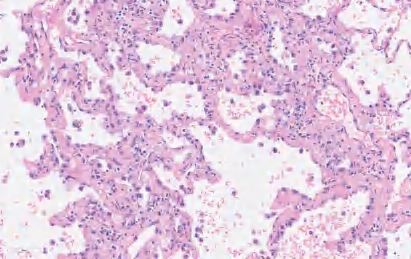

【镜下形态】AAH的细胞为单行排列,细胞间存在间隙,可见钉状细胞和双核细胞,但核分裂象极其罕见(图2-1)。AAH的特点是其增生的细胞依着周围正常的肺泡壁而延续,不像原位癌那样戛然终止。AAH是与鳞状上皮异型增生相对应的一种癌前病变。

图2-1 AAH